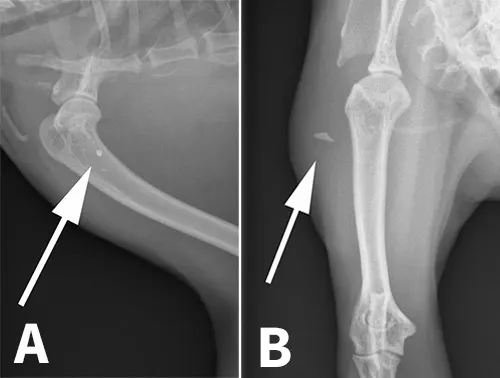

Figure 1: Right lateral (A) and craniocaudal (B) radiographs spanning the right shoulder through the digits.

Right lateral and craniocaudal radiographs spanning the right shoulder through the digits (Figures 1A and B) were obtained to rule out underlying trauma.

Soft tissue swelling was present lateral to the midscapula, extending to the level of the carpus. A triangular mineral opacity, measuring approximately 4 × 8 mm, was seen lateral to the proximal humerus in the craniocaudal view and superimposed over the humerus in the lateral view (Figures 2A and B). No fracture, luxation, or other osseous abnormality was detected. The findings were interpreted as abscessation and/or cellulitis secondary to a penetrating foreign body.